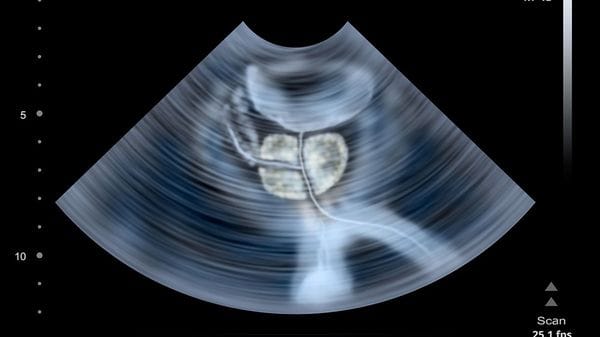

IL SUMMIT INTERNAZIONALE. Bergamo ha ospitato la 13ª edizione della Conferenza internazionale sulle problematiche da trombosi ed emostasi nel cancro.